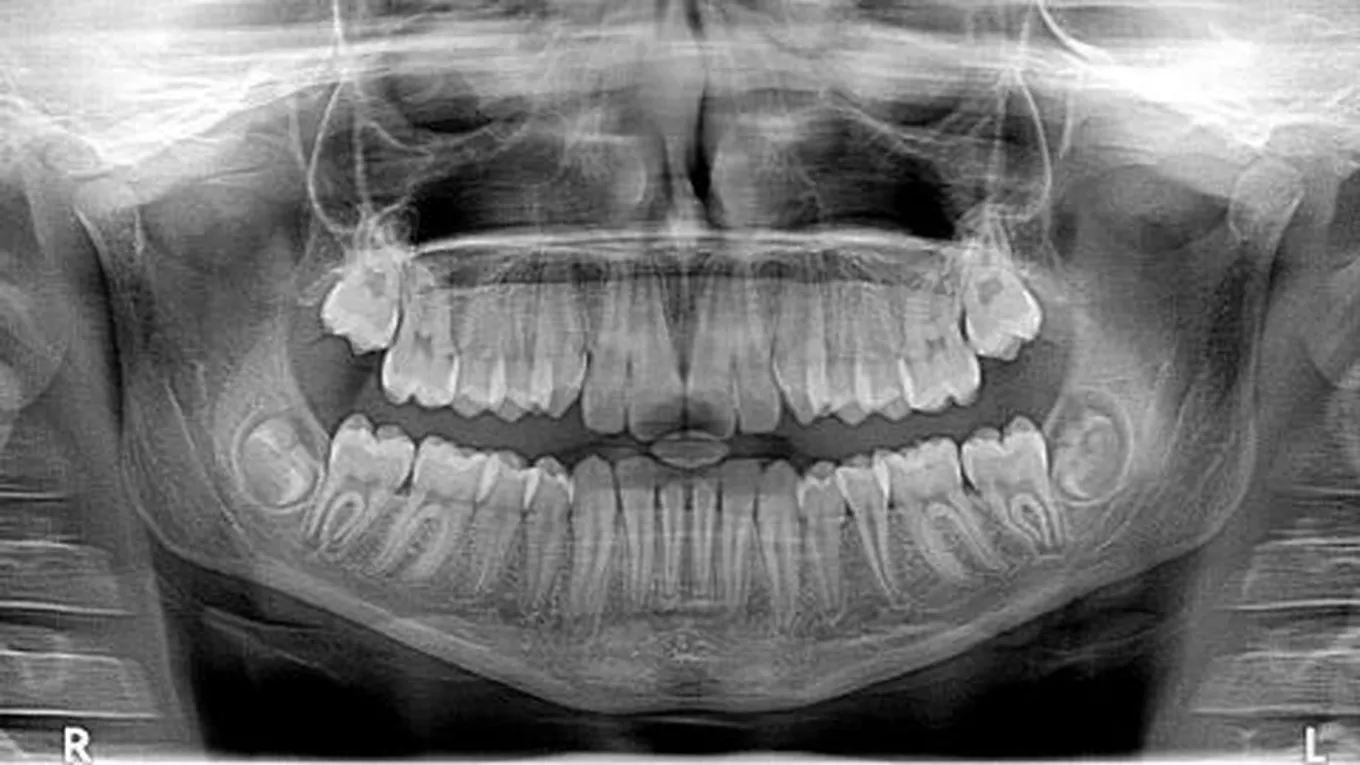

الضروس والأسنان هي أجزاء مهمة في الجسم، وهي موجودة بشكل عام عند الإنسان والثديات من الحيوانات، وتتكون الضروس والأسنان من تركيبات عظمية صلبة تحتوي على عدة أجزاء؛ ومن بينها: جذور مغمورة في اللثة، حيث تحتوي اللثة على جيوب موجودة داخل الفكين.

يكمن الفرق بين الضروس والأسنان في أن الأسنان تكون أمامية أما الضروس فهي الأسنان الخلفية، والسن أو الضرس عبارة عن تجويف يتكون من عدة طبقات؛ وهي: لب السن الذي يتكون من أوعية دموية وأعصاب، ويكون اللب محاطاً بالعاج الذي يعتبر الطبقة الوسطى للسن، ويكون العاج مغلفاً بطبقة المينا ليعطي التاج، والتاج هو الجزء الظاهر من السن أو الضرس، أما جذر السن فيسمى الملاط السني، والجدير بالذكر أن للضروس والأسنان فوائد كثيرة، أهمها: المساعدة على نطق الأحرف والكلمات، ومنح المظهر الجميل للفم والوجه، وتقطيع وسحق الطعام.

القواطع هي الأسنان الموجودة من الأمام وعددها أربعة أسنان، وتكون موجودة في الفكين السفلي والعلوي، حيث يوجد في كل فك سنّين، ويُطلق عليها أيضاً اسم الثنايا، أما العدد الكلي للقواطع فيبلغ ثمانية؛ أربعة في كل فك، أما مهمة القواطع فهي تقطيع الطعام وتمزيقه، والمساعدة على النطق بطريقةٍ صحيحة، ومنح الجمال للوجه.

تتميز الأنياب بحدتها، وبأنها ذات رأس دقيق، ولها شكل مخروطي، ويبلغ العدد الكلي لها أربعة أنياب، حيث يوجد اثنان في كل فك، ومهمتها مساعدة القواطع على تمزيق الطعام.

الضواحك هي الأضراس الأمامية، ويُطلق عليها عليها اسم النواجذ، وتتميز بأن تيجانها أكبر من الأنياب والقواطع، ويبلغ عددها الكلي ثمانية ضواحك، حيث يوجد اثنين بجانب كل ناب، أي أربعة ضواحك في كل فك، ووظيفتها طحن الطعام.

الطواحن هي الأضراس الخلفية التي تطحن الطعام، وتتميز بأن حجمها كبير، وتوجد إلى جانبي الضواحك، وهي أكبر حجماً منها، والتاج الخاص بها يكون سطحاً ماضغاً، ويبلغ عددها الكلي اثني عشر طاحناً، ستة في الفك السفلي وستة في الفك العلوي، وهي أقوى الأسنان والضروس.

يُطلق على ضروس العقل أيضاً اسم الضرس الثالث، وهي آخر الأسنان التي تنشأ، وتظهر عند الإنسان بعد سن البلوغ، وعادةً تظهر في سن متأخرة، ما بين سن الثامنة عشرة والخامسة والعشرين، وعددها أربعة ضروس، وفي بعض الأحيان تظل مطمورةً في اللثة، ولا تظهر إلا بإجراء عملية جراحية للتخلص منها، وخصوصاً إن كانت تسبب الألم، ورغم تسميتها بأضراس العقل إلا أنه لا علاقة لها بنمو العقل.